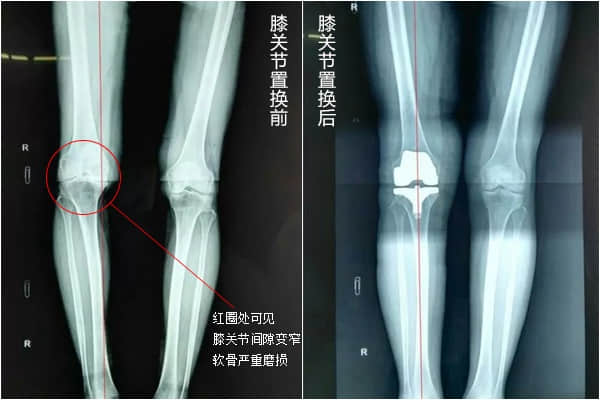

• 换膝盖要花多少钱?膝关节置换手术的优点有哪些?

膝关节位于大腿骨和小腿骨连接处,健康的膝关节能够自由地活动,是因为关节表面覆盖一层滑润的软骨组织和关节周围有强健的肌肉。 软骨是一层光滑的软组织,它覆盖在大腿骨和小

• 膝关节置换手术要花多少钱?关于这台手术你要了解的还有很多……

当所有非药物和药物疗法都无效,骨关节炎已经发展到晚期,患者遭受持续严重的关节疼痛和功能障碍时,可考虑进行关节置换术。医生会根据患者的年龄、体重、活动水平、膝关节大小,形状以及整体健康状况制定手术方案,也不一定换掉整个关节,也可换掉一部分关节(单髁关节置换术),大部分患者手术次日就可下地先走,康复后可很大程度的恢复日常功能和生活质量。不过人工关节毕竟有使用寿命,因此骨关节炎的治疗原则是:从保守无创治